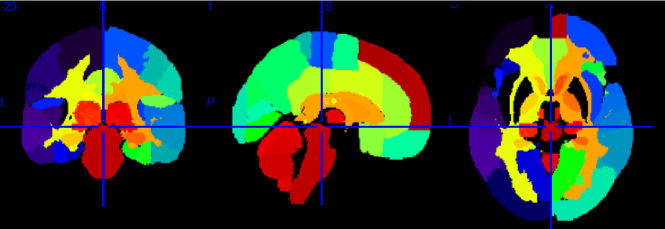

We explore genomewide associations with brain volume difference in terms of voxels; we also perform the same analysis based on groups of voxels, which is the focus of this work. This region of interests (ROIs) approach is a type of dimensionality reduction method that allows for information on local neighborhoods of voxels to be pooled, and reduces possible noise that associates with performing analysis using the entire brain voxels, we denote this as the region-wide study. In order to conduct the experiment using 119 ROIs, we extracted voxels from each brain region, and computed the average Jacobian scores (per region) that make up the 119 different brain regions from the GSK CIC Atlas as shown in Fig. 1, which is based on the Harvard-Oxford atlas with a 6-level hierarchy. To extract the corresponding voxels from each brain region in the atlas, we used the FLIRT linear registration tool from FSL (Jenkinson and Smith (2001), Jenkinson et al. (2002), Smith et al. (2004), and Woolrich et al. (2009)) in order to register the brain atlas to our template scan. This allows us to extract voxels of different brain regions from the subject’s scan and the registered atlas by direct comparison. We then used the average per-region Jacobian scores from each of the 119 ROIs as the response into genomewide association.

Figure 1: Plots showing from left to right: Coronal, Sagittal and Axial views of GSK CIC Atlas, color coded by the 119 region of interests.